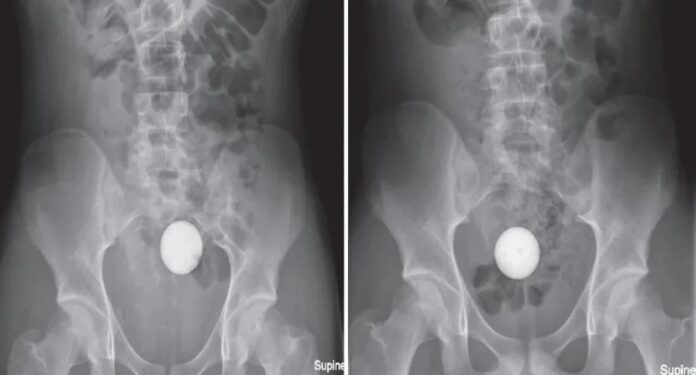

根据X光照,少年的乙状结肠,也就是大肠和直肠连接处出现白色异物,看起来很像鸡蛋,实际上却是一颗完整的高尔夫球。他坦言没有任何不适,但无法透过排便自行移除,因此感到非常惊慌,只好鼓起勇气告诉母亲,并被紧急带往皇家阿德莱德医院求助。

医生们尝试了吸盘、套索、四爪夹等各种“激进的”手段,高尔夫球依然文风不动。家属希望不要再采取物理移除方式,团队最后开了1公升泻药, 3小时后高尔夫球成功排出,而且没观察到肠道受损证据。

该医疗团队将这起特殊案例发表于《外科病例报告》,论文写道,高尔夫球具特殊属性,大尺寸、球体形状、表面小凹洞及不可压缩性都阻碍了形成吸力的密封环境,若试图从结肠取出,便会构成技术性挑战。他们建议若未来遇到类似病例,且患者没有肠道功能障碍,可尝试给予泻药,在不需手术干预的状况下排出异物。